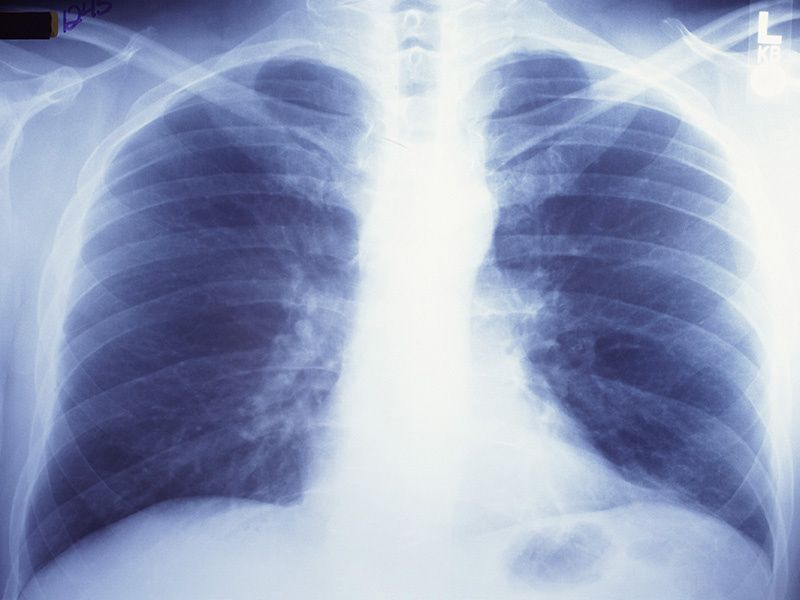

infectious-disease Vaccination Plus Breakthrough Infection Might Give ‘Super Immunity’ Against New Variants